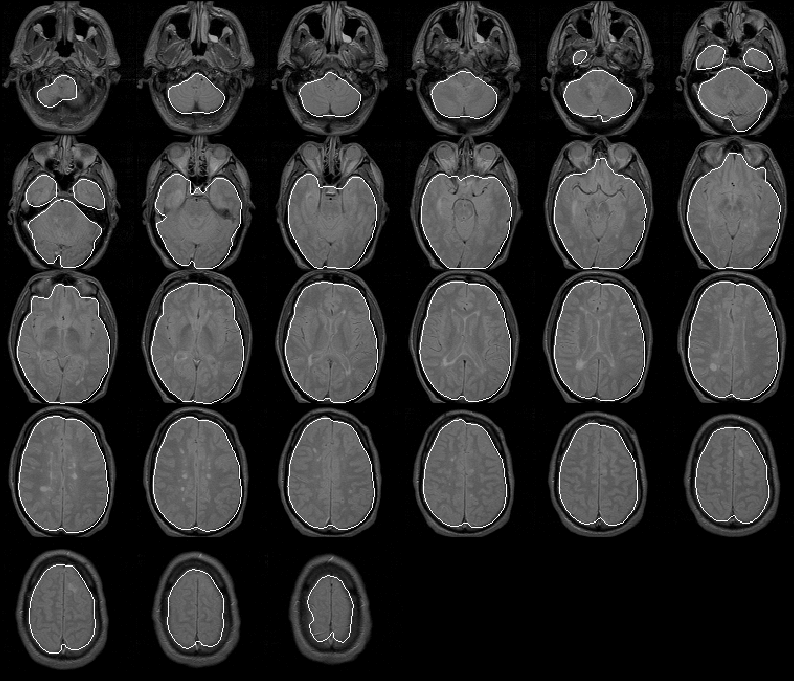

8.5.4 Data Set 4

The final brain mask for Data Set 4 is shown in Figure 8.24. Again, the mask appears to be very accurate. Very small errors occur in slices 11 through 14 where the Generate Final Brain Mask process mistakes bright regions near the forehead as brain. Expert evaluation of the mask is left for future work.

Figure 8.24: The final brain mask for MRI Data Set 4 overlaid on the PD-weighted scan.

8.5.5 Data Set 5

As with the final brain masks of the previous 4 data sets, the final brain mask produced for Data Set 5, shown in Figure 8.25 contains few remarkable errors. The mask misclassifies some small regions of extremely low intensity brain tissue, but is otherwise accurate. The mask will be quantitatively evaluated when expert information becomes available.

Figure 8.25: The final brain mask for MRI Data Set 5 overlaid on the PD-weighted scan.